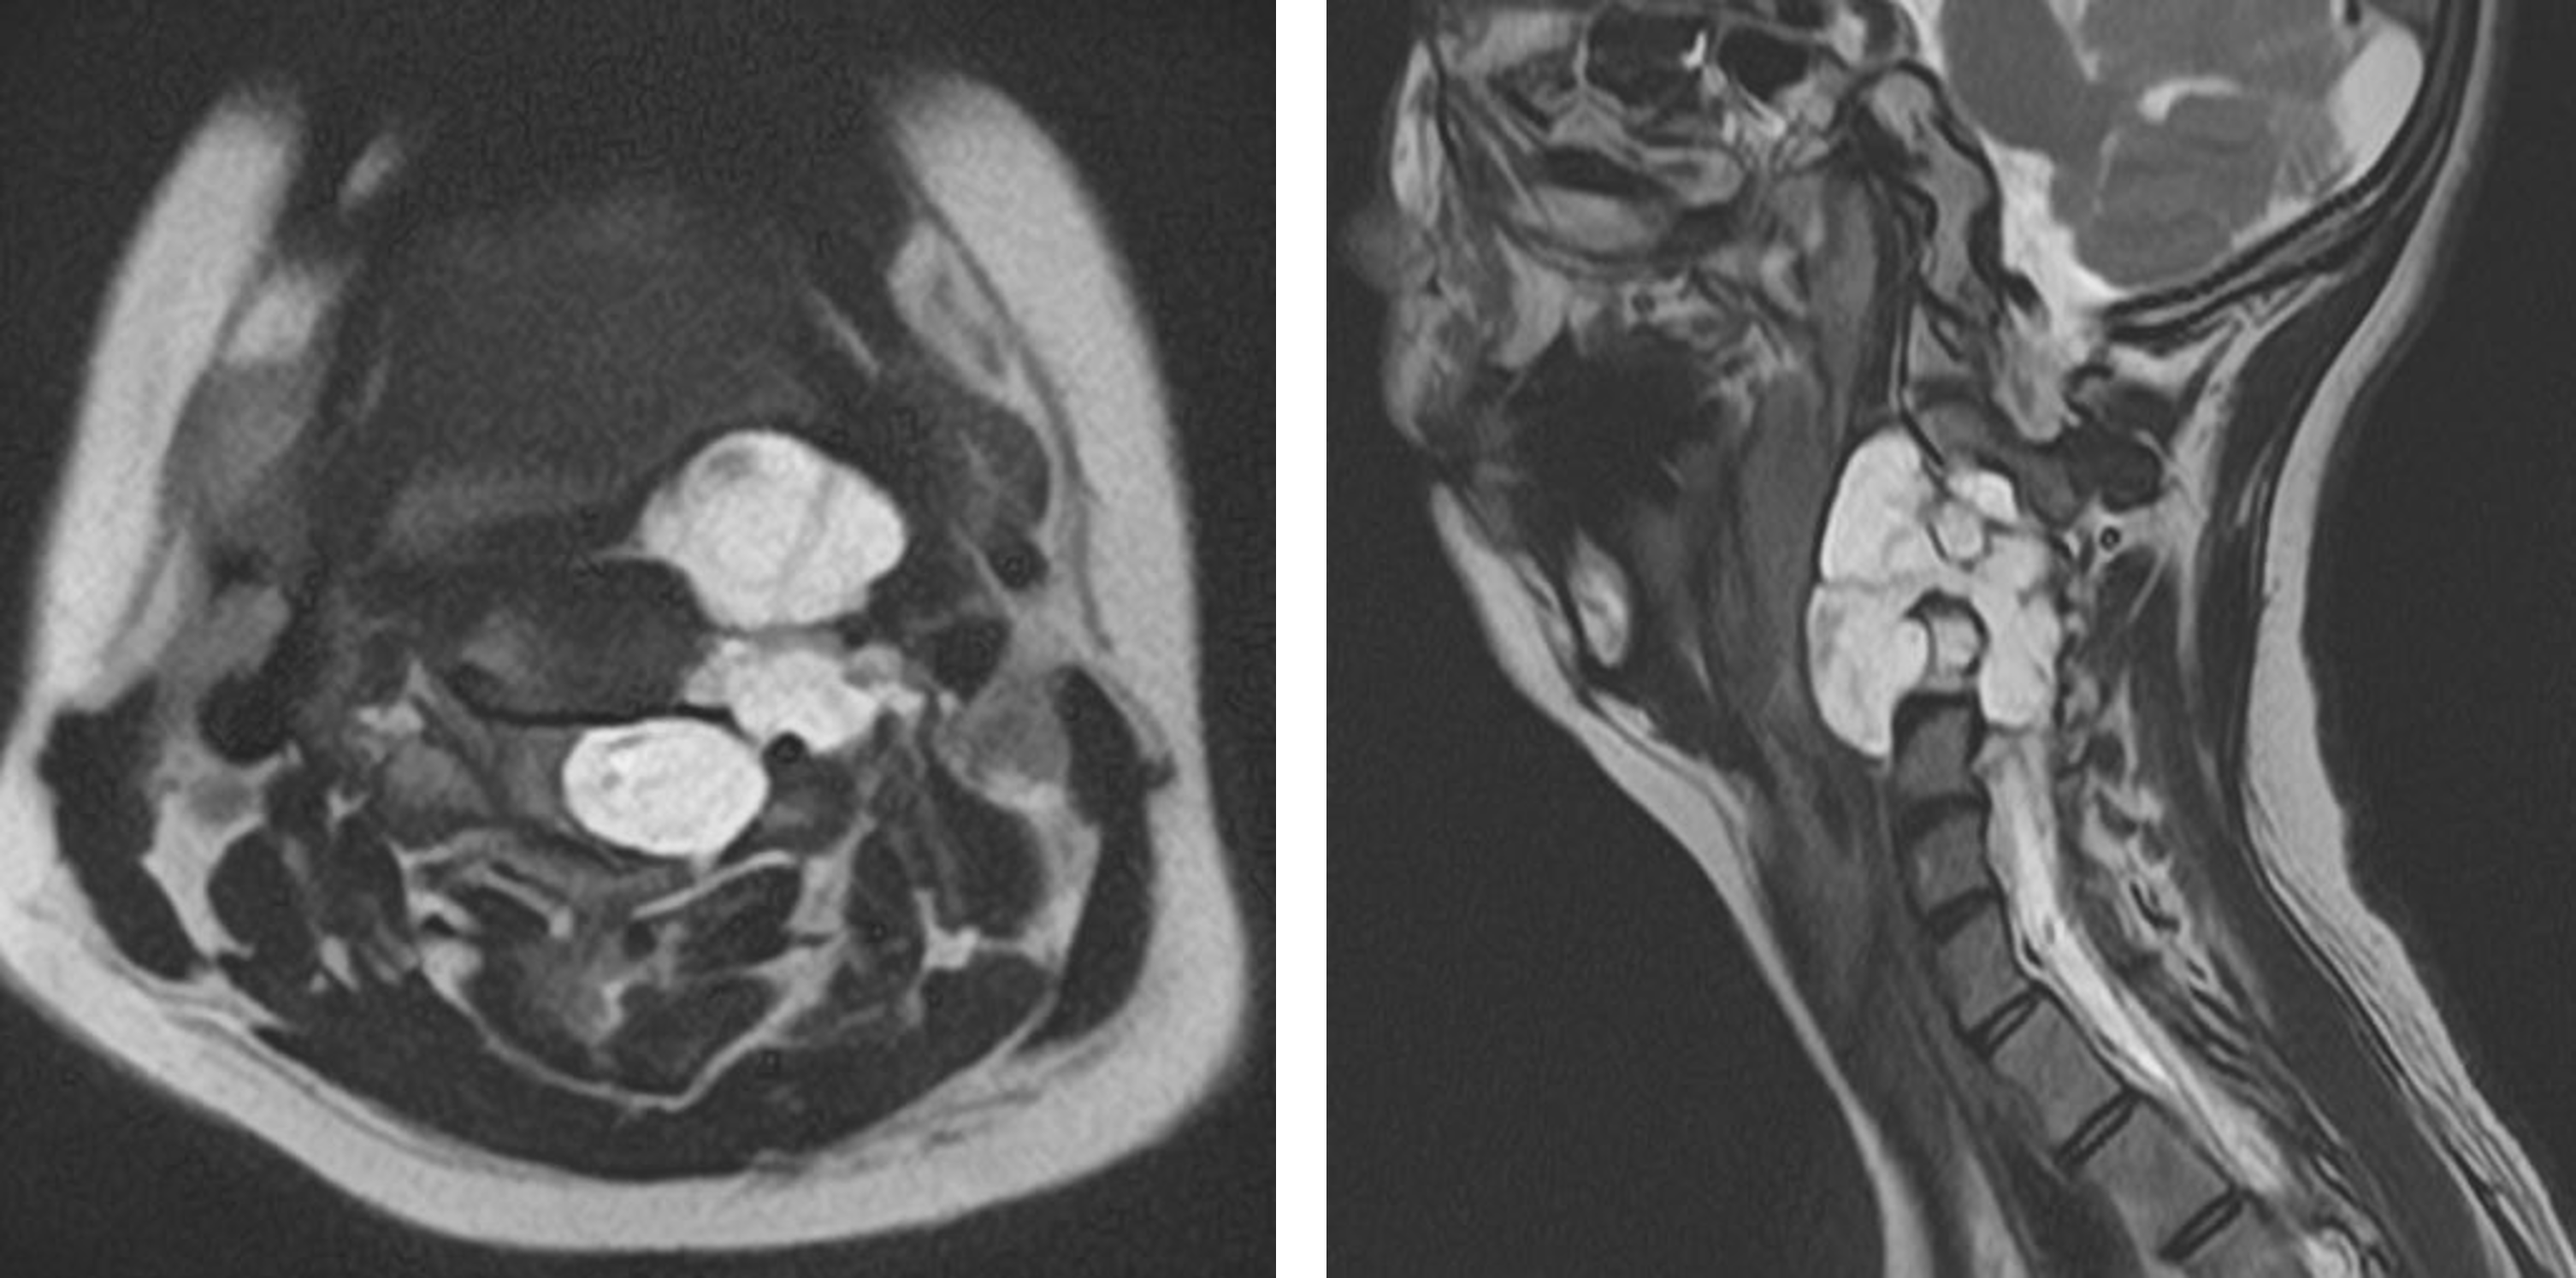

小児がんの中で、脳腫瘍は白血病について第2位の数を占めます。 化学療法の進歩に伴い白血病の大部分は治る病気となってきており、現在は脳腫瘍が死亡率の第1位です。 また、頻度の多い小児脳腫瘍として、星細胞腫、髄芽腫、胚細胞性腫瘍、頭蓋咽頭腫、上衣腫などが挙げられます。

成人では約9割の脳腫瘍が大脳に発生するのに対し、小児では約6割が小脳や脳幹に発生します。 また脳の正中部付近に発生しやすく、脳脊髄液の循環障害により水頭症になりやすいことが知られています。 また、この髄液循環障害や急激な増大などにより、頭蓋内圧亢進症状が起こりやすく、緊急で治療を要する場合があります。

また、小児脳腫瘍は組織型が非常に多彩で、正確な病理診断が難しい場合があります。 経験が豊富な病理医による診断および小児脳腫瘍に詳しい脳神経外科医による判断が重要となります。

治療は、外科的治療、放射線治療、化学療法に大別されます。

良性腫瘍は手術摘出により治癒するものもあります。画像誘導手術や顕微鏡、内視鏡などの技術を用いて、摘出率を向上させ合併症の少ない治療を行っています。

悪性脳腫瘍の場合は、外科的治療だけでは治癒出来ず、外科的治療、放射線治療、化学療法の3つを組み合わせる治療が必要です。

悪性神経膠腫、髄芽腫、胚細胞性腫瘍などの腫瘍の場合は、診断が確定した段階で、速やかに化学療法や放射線療法を行います。

今まで成績の悪かった悪性度の高い腫瘍や再発性腫瘍に対しても、定位放射線治療や大量化学療法を行うことにより生存が得られるようになってきております。

更に、脳腫瘍も長期生存例が増えるに従い、晩期障害についてのfollow upも必要となってきています。当院では、晩期障害を減らす試みも行っており、治療後も長期間follow upしております。